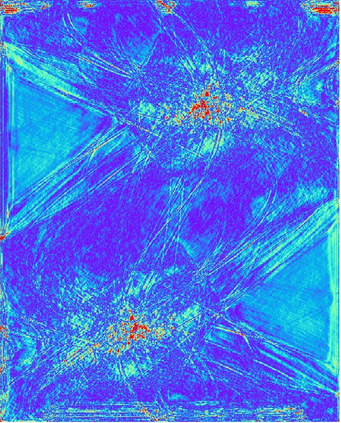

Low-Dose Computed Tomography (LDCT) technique, which reduces the radiation harm to human bodies, is now attracting increasing interest in the medical imaging field. As the image quality is degraded by low dose radiation, LDCT exams require specialized reconstruction methods or denoising algorithms. However, most of the recent effective methods overlook the inner-structure of the original projection data (sinogram) which limits their denoising ability. The inner-structure of the sinogram represents special characteristics of the data in the sinogram domain. By maintaining this structure while denoising, the noise can be obviously restrained. Therefore, we propose an LDCT denoising network namely Sinogram Inner-Structure Transformer (SIST) to reduce the noise by utilizing the inner-structure in the sinogram domain. Specifically, we study the CT imaging mechanism and statistical characteristics of sinogram to design the sinogram inner-structure loss including the global and local inner-structure for restoring high-quality CT images. Besides, we propose a sinogram transformer module to better extract sinogram features. The transformer architecture using a self-attention mechanism can exploit interrelations between projections of different view angles, which achieves an outstanding performance in sinogram denoising. Furthermore, in order to improve the performance in the image domain, we propose the image reconstruction module to complementarily denoise both in the sinogram and image domain.